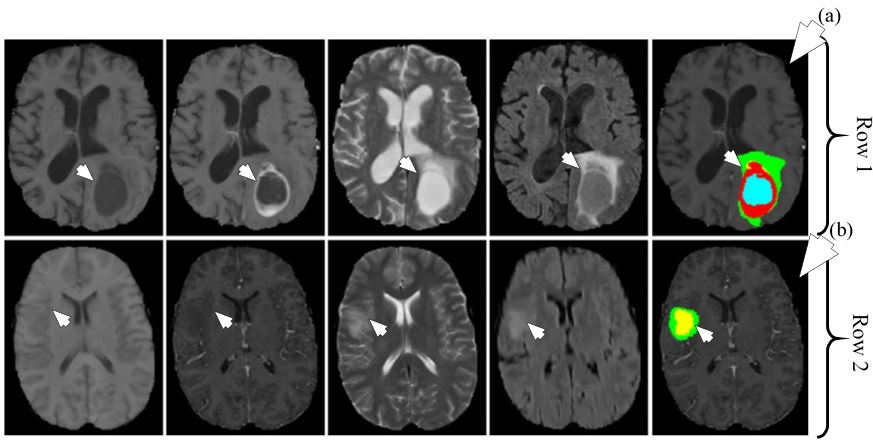

As per WHO report, liver cancer has been the second major cause of death among all cancers. Detection of liver tumor from CT images is tough task appearance variability, fuzzy boundaries and heterogeneous densities, shapes and sizes of lesions. Earlier applications of ML had limited performance due to their dependence on hand-made feature extraction algorithms. In here (58), DL-based framework has been used for segmentation for liver tumor.

A CNN architecture is used as the DL-based framework. The CNN consisted of two convolutions, two max-pooling, one fully connected and one Softmax layer. Three ML algorithms which are AdaBoost, Random Forest (RF) and SVM were used for benchmarking the results. The images were pre-processed and patches were extracted from the images. Each patch was labelled positive if more than 50% of it contained tumor cells and negative otherwise. All the patches were fed into the CNN for training and testing. A dataset of 30 CT images was collected for the experiment. The CT images were divided into two categories of tumor and non-tumor images. The comparison results show DM coefficient at 80.06% for the given method, 79.78% for SVM, 79.47% for RF and 75.67% for AdaBoost. The segmentation system model is visualised in Figure 32. The segmentation output is given in Figure 33. The results have shown considerable improvement over ML based techniques, however, there was a clear potential of improvement in terms of accuracy.

Figure 32Segmentation of CT liver tumor.

Figure 33Segmentation of CT liver tumor for four patients using AdaBoost (purple) in row one, RF (green) in row two, SVM (blue) in row three and CNN (red) in row four. GT is shown in yellow in all rows (reproduced with permission from (54)).